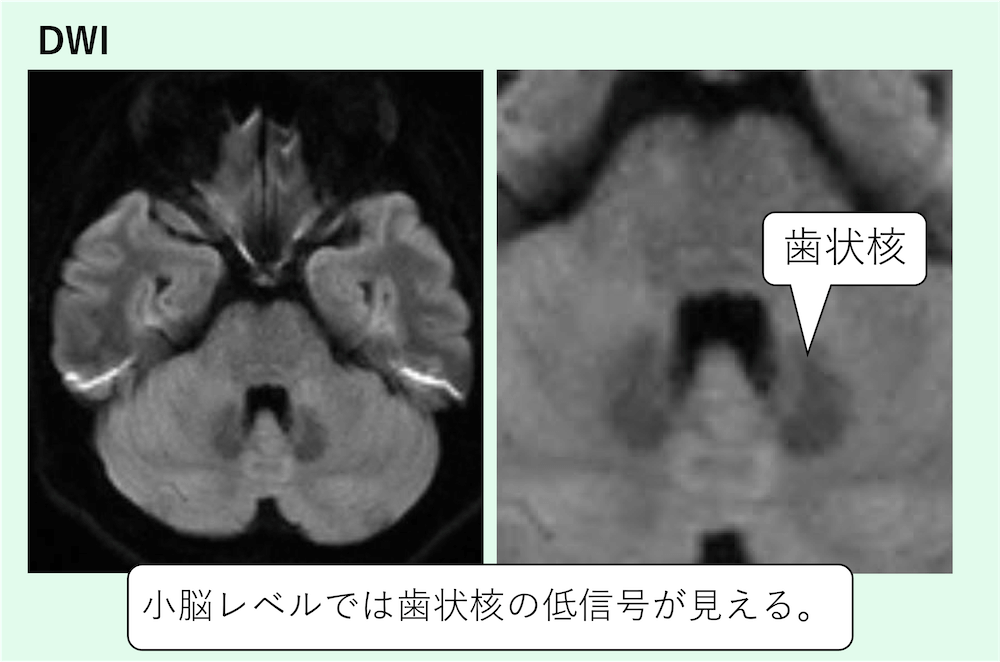

3)小脳歯状核(dentate nucleus)

- 歯状核:鉄・石灰化・一部薬剤/沈着など多要因で低信号になり得る。

小脳レベルでは歯状核の低信号が見えます。